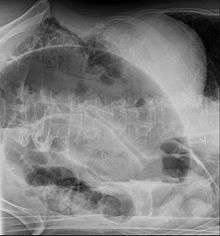

An x-ray of a person with a small bowel volvulus.

After taking a thorough history, the diagnosis of colonic volvulus is usually easily included in the differential diagnosis. Abdominal plain x-rays are commonly confirmatory for a volvulus, especially if a "bent inner tube" sign or a "coffee bean" sign are seen. These refer to the shape of the air filled closed loop of colon which forms the volvulus. Should the diagnosis be in doubt, a barium enema may be used to demonstrate a "bird's beak" at the point where the segment of proximal bowel and distal bowel rotate to form the volvulus. This area shows an acute and sharp tapering and looks like a bird's beak. If a perforation is suspected, barium should not be used due to its potentially lethal effects when distributed throughout the free infraperitoneal cavity. Gastrografin, which is safer, can be substituted for barium.